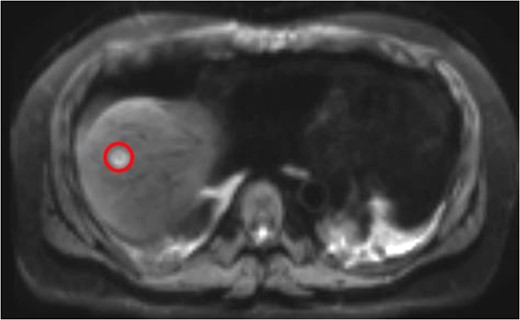

Magnetic resonance imaging (MRI) after the initial chemotherapy cycle demonstrated a liver segment VIII 13-mm metastasis and indeterminate 5-mm lesions in segments VI and IV. Interventional radiology services performed a right portal vein embolization. On subsequent postembolization MRI, hepatic lesions were indiscernible, and liver remnant volumetrics increased from 21 to 35%.

Neoadjuvant therapy was completed 1 month before surgical intervention. The patient underwent bilateral ureteral stents placement and an exploratory laparotomy in the lithotomy position. Intraoperative ultrasonography localized the tumor without showing any unexpected lesions. A right extended hepatectomy proceeded in the standard manner (Figs 3 and 4).